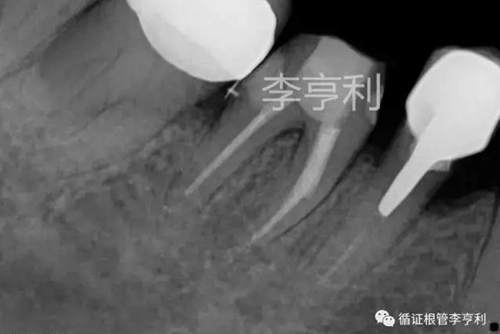

術(shù)前片 (2017-05-16)

輔助檢查:遠(yuǎn)中角度投射根尖片,見斷械影像移向近中,故判斷器械分離于近中頰根,根尖周未見明顯異常 。

遠(yuǎn)中角度投射,紅色箭頭為分離器械 (2017-05-16)

術(shù)前診斷:46根管已開始治療,根尖周正常組織,伴發(fā)器械分離 (previously initiated treated with normal apical tissues, complicated by separated instrument)。